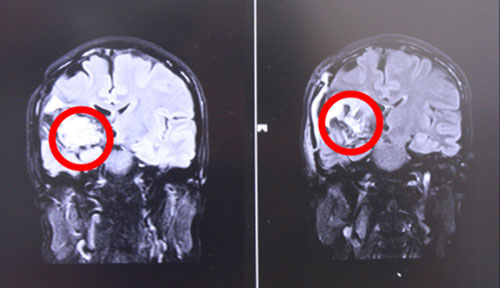

左側(cè)為術(shù)前,右側(cè)為術(shù)后,術(shù)后紅圈內(nèi)腫瘤物基本消失

術(shù)后,患者頭暈癥狀好轉(zhuǎn),面部抽搐也未發(fā)作,肢體功能明顯好轉(zhuǎn),生命體征平穩(wěn)。據(jù)侯主任介紹,經(jīng)過一段時間的康復(fù),患者即可恢復(fù)生活自理能力。目前患者已經(jīng)出院。針對此次案例,侯主任語重心長地說,作為一名神經(jīng)外科醫(yī)生,不僅要做好每一個手術(shù),確;颊呱踩那疤嵯拢M可能全切腫瘤。更重要的是要針對每位患者的特殊情況特殊對待,拿捏好手術(shù)的度,不能一味保守或者冒進地對腫瘤不作為或不管不顧全切。侯主任根據(jù)自己臨床多年的經(jīng)驗準(zhǔn)確判斷出病人損傷可以恢復(fù),險中求穩(wěn)求全,果斷做了全切手術(shù),從中我們也看到了一代專家的專業(yè)態(tài)度和敬業(yè)精神。